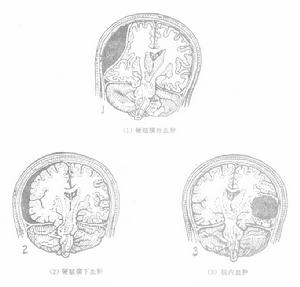

高速的彈片或槍彈等投射物穿透腦膜入顱後,在腦內形成傷道。傷道腦的病理改變為:(1)原發傷道區:指傷道中心區,內含有毀損與液化的腦組織碎塊,出血和血塊。顱骨碎片,頭髮,泥沙及彈片或槍彈等。碎骨片常位傷道近端。彈片或槍彈則位於傷道遠側。損傷的腦膜、腦血管和腦組織出血,易在傷道形成硬膜外,硬膜下,腦內或腦室血腫。傷道內血腫的部位,可位於近端,中段和遠端。(2)其外周為腦挫裂傷區:是由於高速投射物穿入顱腔後的瞬間,在腦內形成暫時性空腔,產生超壓現象,衝擊波向周圍腦組織傳遞,使腦組織頓時承受高壓和相繼的負壓作用而引起腦挫裂傷。病理徵象表現為點狀出血和腦水腫帶。(3)位於腦挫裂傷區周圍為腦震盪區。